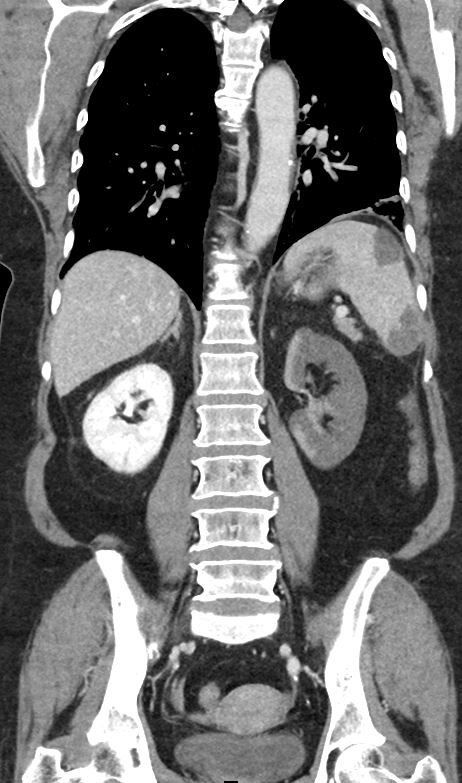

On the coronal sections of computed tomography (CT), bilateral renal infarctions (blue arrows) and several splenic infarctions (green arrows) are noted. Of particular interest, part of the clot totally occluding the left renal artery visibly extends into the aorta (red arrow). The vascular reconstruction image is remarkable for the absent left kidney, the unusual contour of the right kidney and the abnormal splenic blush.

Classic emergency medicine teaching dictates that when a patient with atrial fibrillation has abdominal pain “out of proportion” to the examination, one must consider mesenteric ischemia. Although the bowels clearly carry the highest embolic risk for abdominal viscera, other organs are at risk as well. This case illustrates a rare constellation of segmental splenic infarcts and bilateral renal infarction, with complete left renal artery occlusion stemming from multiple emboli.